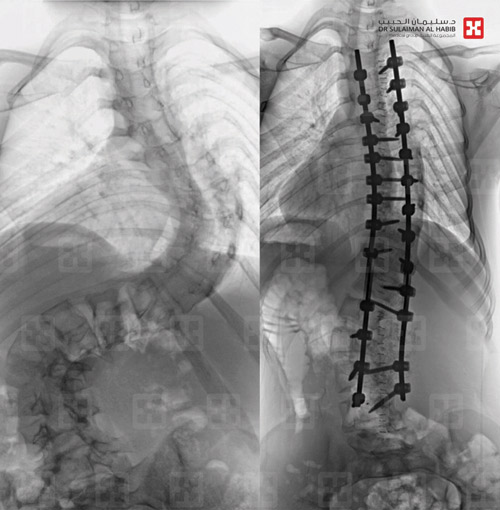

أجرى قسم جراحة العمود الفقري بمستشفى الدكتور سليمان الحبيب بالقصيم «4» عمليات ناجحة، لتقويم العمود الفقري وتثبيت ودمج الفقرات، خلال «48» ساعة لأشخاص مصابين بالجنف، وأنهت هذه العمليات معاناة المرضى مع أعراض ومضاعفات المرض التي اتسمت بالحدة والتنوع.

وقال د.صلاح الدين خليفة استشاري جراحة العمود الفقري بالمستشفى، إن الحالات التي تمت معالجتها تفاوتت درجة الانحراف عندها بين «45 إلى 90» درجة، وتراوحت أعمارها بين « 11 إلى 38» سنة، وعانى بعضها من أعراض كبروز الظهر وعدم تساوي الكتفين والخصر وبروز أحد الوركين وجانب من القفص الصدري، وصعوبة ممارسة الحياة اليومية بصورة طبيعة.

وأضاف د.خليفة أن أكثر الحالات تعقيداً تعود إلى سيدة عمرها «38» سنة، وبلغ نسبة الانحراف عندها «90» درجة، وتكللت عمليتها ولله الحمد بنجاح كبير، وأكد أن المريضة بدأت في الوقوف والتحرك في اليوم الأول للعملية، كما أنها استعادت المظهر القويم، بعد تعديل وضعية الحوض والكتف، إضافة إلى أن طولها مع النجاح الكبير للتعديل زاد بنحو «6» سم، وخرجت من المستشفى وهي بصحة جيدة بعد أن أمضت «6» أيام قيد التنويم والعناية الصحية الحثيثة.